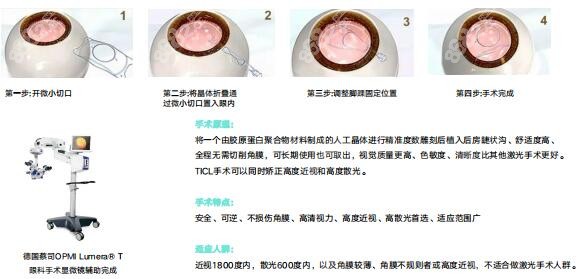

对于近视手术,成都高新睛彩眼科提供多种选择,包括准分子激光、全激光、半飞秒/全飞秒激光、ICL晶体植入等,均是常见的近视手术方式,其中对于高度近视和那些不适合激光手术的患者来说,ICL晶体植入是一项非常有效的治疗方法,可以显著改善视力并降低依赖眼镜或隐形眼镜。

李纲医生毕业于,从事眼科临床工作近30年,在四川地区首先开展全飞秒激光与准分子激光近视手术和ICL晶体植入术,高度近视手术量居国内前列,对超高度近视等复杂屈光病例的治疗有极高造诣,并多次获得屈光领域新技术奖。李纲医生始终遵循患者至上的原则,注重术前的详细咨询和检查,以确保手术的可靠性和有效性。她熟练掌握高度ICL晶体植入手术的操作技巧,并通过个性化治疗方案为每位患者提供更佳的视力改善结果。